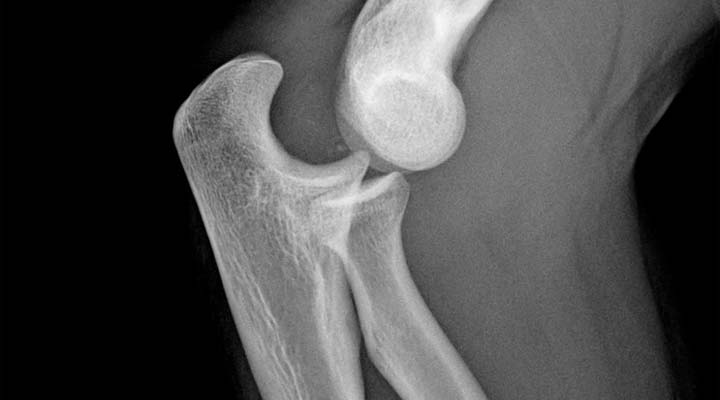

El descubrimiento se ha centrado en las microfracturas óseas, debido a que «en las roturas a mayor escala, el proceso de regeneración celular es distinto», comentó Catalán.

Estas microfracturas se pueden producir con el uso normal del hueso, aunque en deportistas de alto rendimiento son más frecuentes.

Una vez se produce esta microscópica rotura, la presión que se aplica sobre el punto inicial de la fractura es la que genera flexoelectricidad, es decir, que produce una descarga que mata las células de su alrededor.

«Lo que descubrimos es que la muerte celular que desencadena la flexoelectricidad actúa como faro para las células reparadoras, que acuden a regenerar la rotura» afirmó Vásquez-Sancho.

Para que se active la flexoelectricidad en las fracturas «es importante que el hueso trabaje, aunque también, y sobre todo en deportistas, es necesario que repose, para que pueda regenerarse bien la microrotura», aclaró Catalán.